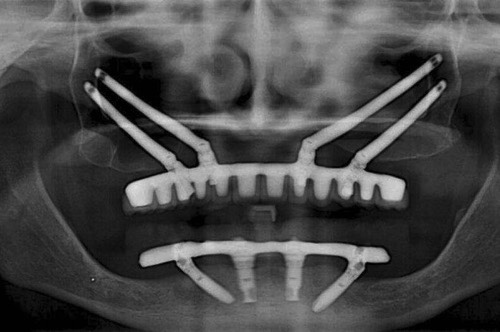

穿顴種植牙是上頜骨嚴重骨吸收情況下的一種有效替代治療方法,也可被用于上頜骨缺損的修復(fù)治療,既避免了大量的植骨手術(shù),且能明顯縮短種植治療周期。

效果展示

1. 骨量充足的 1 區(qū)及雙側(cè)缺骨的 2、3 區(qū):建議 2-4 顆傳統(tǒng)軸向種植體位于 1 區(qū),雙側(cè) 2 或 3 區(qū)各加一顆顴骨種植體。

2. 骨量充足的 1 區(qū)及一側(cè)缺骨的 2、3 區(qū):建議缺骨側(cè) 2、3 區(qū)一顆顴骨種植體,對側(cè) 2、3 區(qū)及 1 區(qū)采用常規(guī)種植體。

3. 缺骨的 1 區(qū)及骨量充足的 2、3 區(qū):一顆顴骨前種植體加后方常規(guī)種植體即可。

4. 1、2、3 區(qū)均缺骨:4 顆顴骨種植體即可。